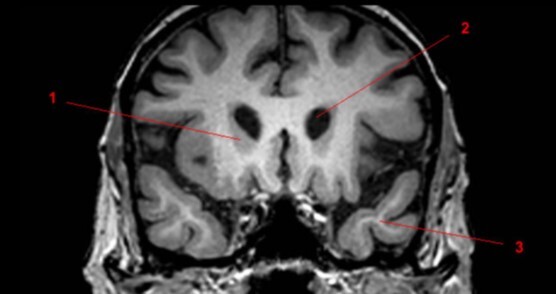

Label 1-5

Label 1-6

1=Frontal bone

2-Falx cerebri

3-Left frontal lobe

4-Left anterior cerebral artery

5-Right temporal lobe

6-Temporal horn of left lateral ventricle